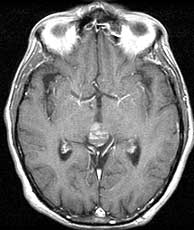

Diagnosis: Vein of Galen malformation

The VOG is the confluence of the basal vein of Rosenthal and the internal cerebral veins. It joins the inferior sagittal sinus to form the straight sinus. The vein of Galen malformation (aneurysm is a misnomer) is an abnormal developmental connection between the VOG and any of the following arteries; anterior cerebrals, anterior and posterior choroidals, lenticulostriates and thalamoperforators. It often presents in the neonatal period with CHF, cranial bruit or seizures. Treatment consists of endovascular embolization and/or surgery. The differential for this case without the angiogram is limited. Perhaps a huge calcified arterial aneurysm or pineal cyst could resemble this. A calcifying pineal region tumor is very unlikely due to the peripheral nature of the calcification. The angio however nails the diagnosis. Related Cases